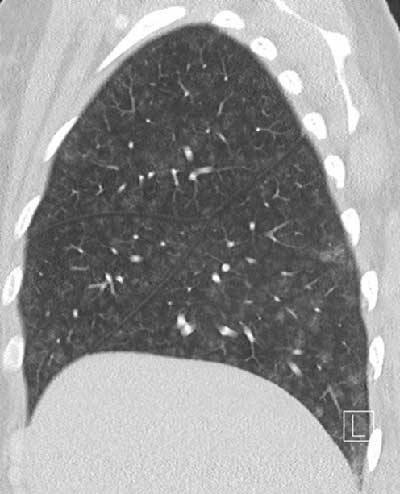

Figure 1

Diffuse groundglass centrilobular nodules without tree-in-bud.